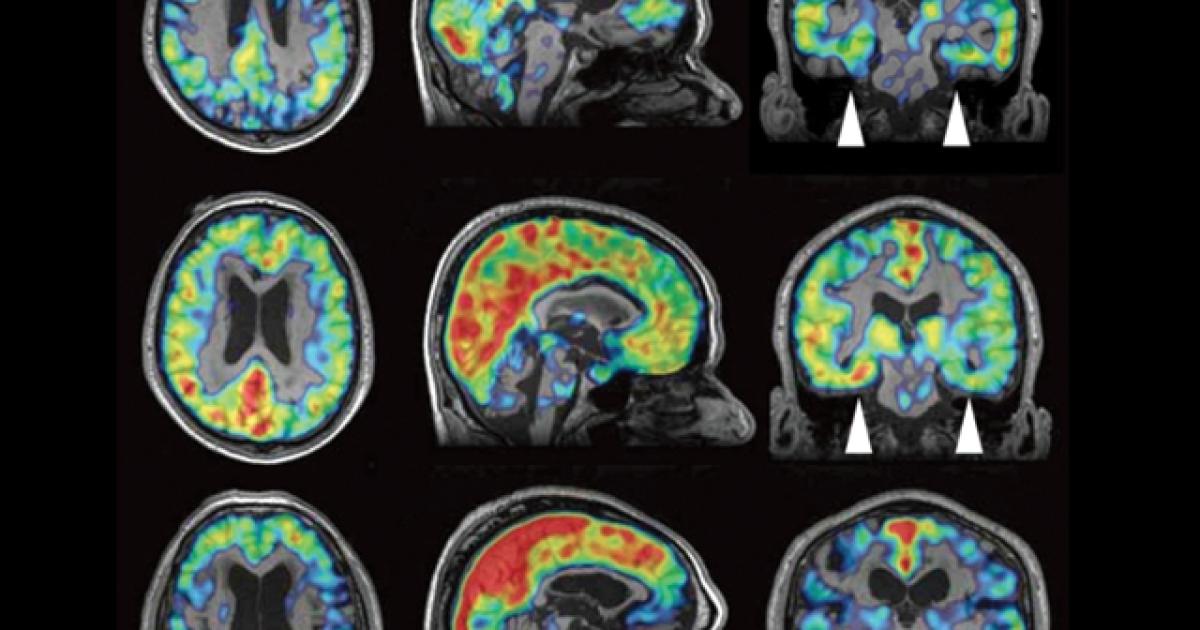

It can only be suspected in people who are at high risk due to repeated head trauma over the course of years during their sports or military experiences. Military soldiers may also develop cte, especially those who have experienced multiple head. Nih chronic traumatic encephalopathy diagnosis conference. Diagnosis of chronic traumatic encephalopathy. Improving diagnosis of cte to fill current gaps in knowledge about the disease, researchers are studying methods to diagnose cte during life, including through the use of experimental pet. After he was diagnosed with dementia and probable cte, former nfl player and sportscaster mike adamle and his wife kim launched the mike adamle project: A diagnosis of cte can only be made after death, when an autopsy can reveal whether the known brain changes of cte are present. How is chronic traumatic encephalopathy (cte) diagnosed?

Improving diagnosis of cte to fill current gaps in knowledge about the disease, researchers are studying methods to diagnose cte during life, including through the use of experimental pet. In a diagnosis that linked one of football's most notorious figures with the sport's most significant health risk, doctors found hernandez had stage 3 cte, which researchers had never seen in. The encephalopathy symptoms can include behavioral problems, mood problems, and problems with thinking. Most documented cases have occurred in athletes involved in striking. The diagnosis was confirmed after the death of a former nfl player at age 63. When cte is suspected, a thorough medical history, mental status testing, neurological exams, brain imaging and more may be used to rule out other causes. Rise above provides patients living with symptoms of cte, and their families, with tools, resources, a supportive community, and most importantly, with hope. Chronic traumatic encephalopathy (cte) is a progressive brain condition that's thought to be caused by repeated blows to the head and repeated episodes of concussion. Military soldiers may also develop cte, especially those who have experienced multiple head. While cte is most common among football and hockey players, many boxers have been noted as having the condition and even baseball players have been diagnosed with cte type degenerative conditions. New criteria aid diagnosis of traumatic encephalopathy syndrome. It's particularly associated with contact sports, such as boxing or american football. Former nfl player confirmed as 1st diagnosis of cte in living patient.